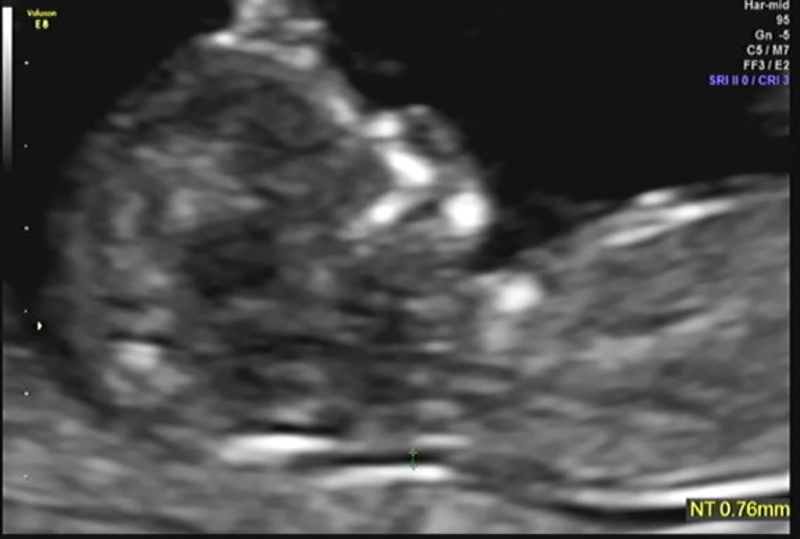

정밀초음파는 1차(10~13주), 2차(20~21주)에 시행되는데, 1차 정밀초음파 검사: 태아목 투명대(NT) 두께 측정으로 태아의 염색체, 심장에 이상이 있는지 확인합니다.보통 2.5mm 미만이 정상입니다(목투명대란 아기를 둘러싼 차양막에서 목까지의 빈 부분입니다.)